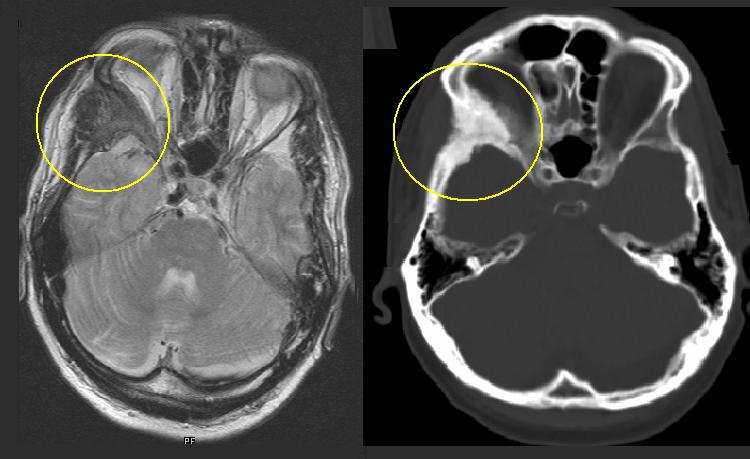

- Tomografia Computerizzata (TC), in particolare Cone Beam (CBCT): questa metodica è superiore alla radiografia per la valutazione di regioni anatomiche complesse come il distretto cranio-facciale o il bacino. Permette una stima precisa dell’estensione della lesione e dei suoi rapporti con le strutture neurovascolari adiacenti.

- Risonanza Magnetica Nucleare (RMN): utile per la diagnosi differenziale con altre lesioni cistiche e per valutare le regioni ossee interessate.

- episodi di compressione nervosa: nelle localizzazioni cranio-facciali, l’espansione ossea può comprimere i nervi cranici, causando parestesie, disturbi visivi (calo o perdita della vista), uditivi e obliterazione dei seni nasali;

- manifestazioni cranio-facciali specifiche: possono includere occhi sporgenti (bulging eyes), malocclusione o disallineamento mascellare e denti disallineati o malformati.